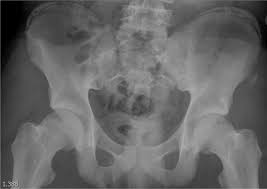

Apophyseal Avulsion Fracture Ric Size from i1.wp.com They are serious injuries that most often occur in people aged 65 and older. People who fracture their hip sometimes need surgery to fix the fracture or replace the hip. These injuries can be extremely painful, and may take months to heal. An avulsion fracture is a fracture in which part of the bone breaks off from the rest of the bone. Sometimes you can get an avulsion fracture in other bones, such as the hand. They are more common in children avulsion fractures are caused by trauma. What causes a hip fracture? Ebraheim's educational animated video describes the condition of avulsion fractures around the hip in adolescence.

Timely, accurate diagnosis is imperative so proper treatment can be initiated. Ebraheim's educational animated video describes the condition of avulsion fractures around the hip in adolescence. Call 999 and ask for an ambulance. I was doing high jump and twisted my body and in the process my muscle ripped my growth bone off. Hip fractures are classified according to their anatomical location as intracapsular, which involves the femoral head and neck, and extracapsular, which includes intertrochanteric, trochanteric, an. With an avulsion fracture, an injury to the bone occurs near where the bone attaches to a tendon or ligament. Symptoms of ankle avulsion fracture are similar to ankle sprain. Call your health care provider if your pain doesn't go away, or if you notice swelling. Preparing for an avulsion fracture in the ankle? Avulsion fractures of the hip and. Avulsion fracture of the iliac crest is an uncommon pathology. This happens when a muscle or tendon connected to the hip bone suddenly tightens so hard that it pulls off part of the bone. I am 15 and did it to my hip/ upper pelvic bone.

With an avulsion fracture, an injury to the bone occurs near where the bone attaches to a tendon or ligament. Anyone can suffer an avulsion fracture of the ankle, but athletes and children are more prone to them than the rest of us. This happens when a muscle or tendon connected to the hip bone suddenly tightens so hard that it pulls off part of the bone. Ebraheim's educational animated video describes the condition of avulsion fractures around the hip in adolescence. An avulsion fracture occurs when a small chunk of bone attached to a tendon or the hip, elbow and ankle are the most common locations for avulsion fractures in the young athlete. If you think you've fractured your hip, you'll need to go to hospital as soon as possible. In acute avulsion fractures, there is usually a clear preceding traumatic incident. When to seek medical help. The causes of hip fracture are very different in young and elderly patients. With age, the bones can become weak and brittle. Other causes include cancer and injury. They usually happen when a bone is moving one way, and a tendon or ligament is suddenly pulled the opposite way. Hip apophyseal injuries in young athletes are a fairly rare problem, and often go unrecognized by health professionals.

Acute Avulsion Of The Iliac Crest Apophysis In An Adolescent Indoor Soccer from www.jbsr.be I am 15 and did it to my hip/ upper pelvic bone. An avulsion fracture is a fracture in which part of the bone breaks off from the rest of the bone. When the fracture happens, the tendon or these fractures most often affect bones in the elbow, hip, and ankle. What causes a hip fracture? There are numerous sites at which these occur. Hip pain in children is always a potentially serious and needs urgent assessment. Teenagers are more likely to have this injury than younger children. Hip fractures can limit mobility and independence.

Pain in the hip area may be referred from the knee joint or from structures in the inguinal canal, testis (including torsion) and lower abdomen, or from the lower back. Teenagers are more likely to have this injury than younger children. The causes of hip fracture are very different in young and elderly patients. Other causes include cancer and injury. Hip fracture occurs in approximately 341,000 persons in the united states each year. Read about causes, treatment options, available mobility devices, tips for recovery, and more. This happens when a muscle or tendon connected to the hip bone suddenly tightens so hard that it pulls off part of the bone. In acute avulsion fractures, there is usually a clear preceding traumatic incident. A hip fracture is a break in the bones of your hip. A hip fracture is a common injury, especially in people with osteoporosis. I was doing high jump and twisted my body and in the process my muscle ripped my growth bone off. A broken hip in older people is often partly the result of weakening bones from osteoporosis. This most commonly occurs at the ischial tuberosity where the hamstrings attach, or the iliac pain at the bony part on the front of the hip may be an anterior superior iliac spine avulsion fracture.